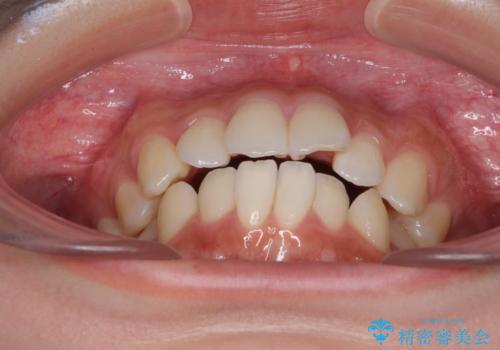

前歯のデコボコと突出感 インビザラインで改善

- 上下前歯のデコボコを気にして来院された患者様です。

インビザラインによる上下歯列の側方拡大と後方移動、IPR(歯と歯の間を削る)にるスペースの獲得により歯列を整えることとしました。